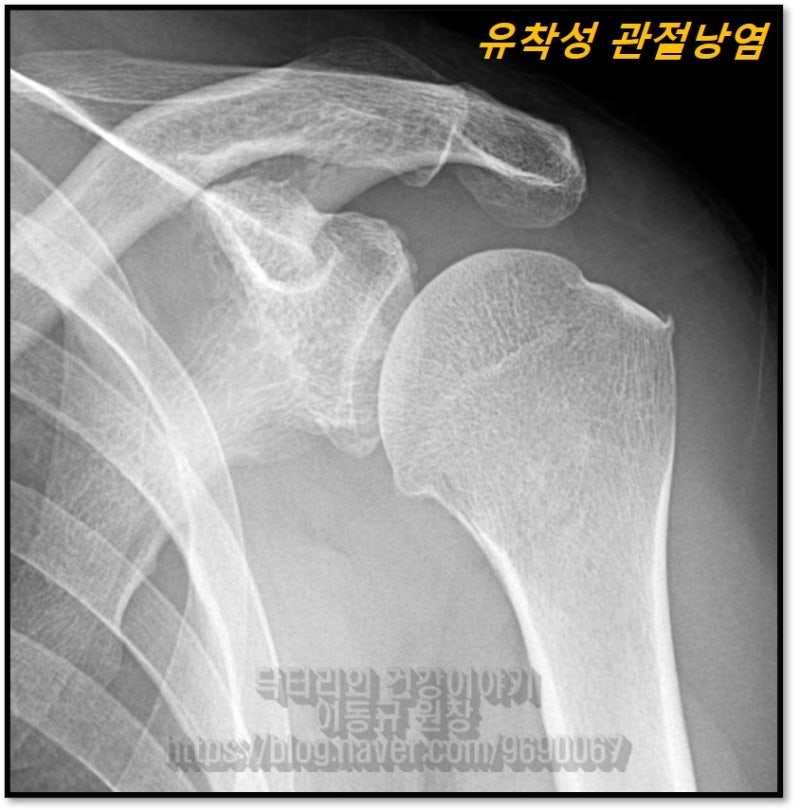

X-ray 상에서는 상완골 대결절 극상근 부착 부위에 미세한 석회와 골극이 자라난 것이 관찰됩니다.